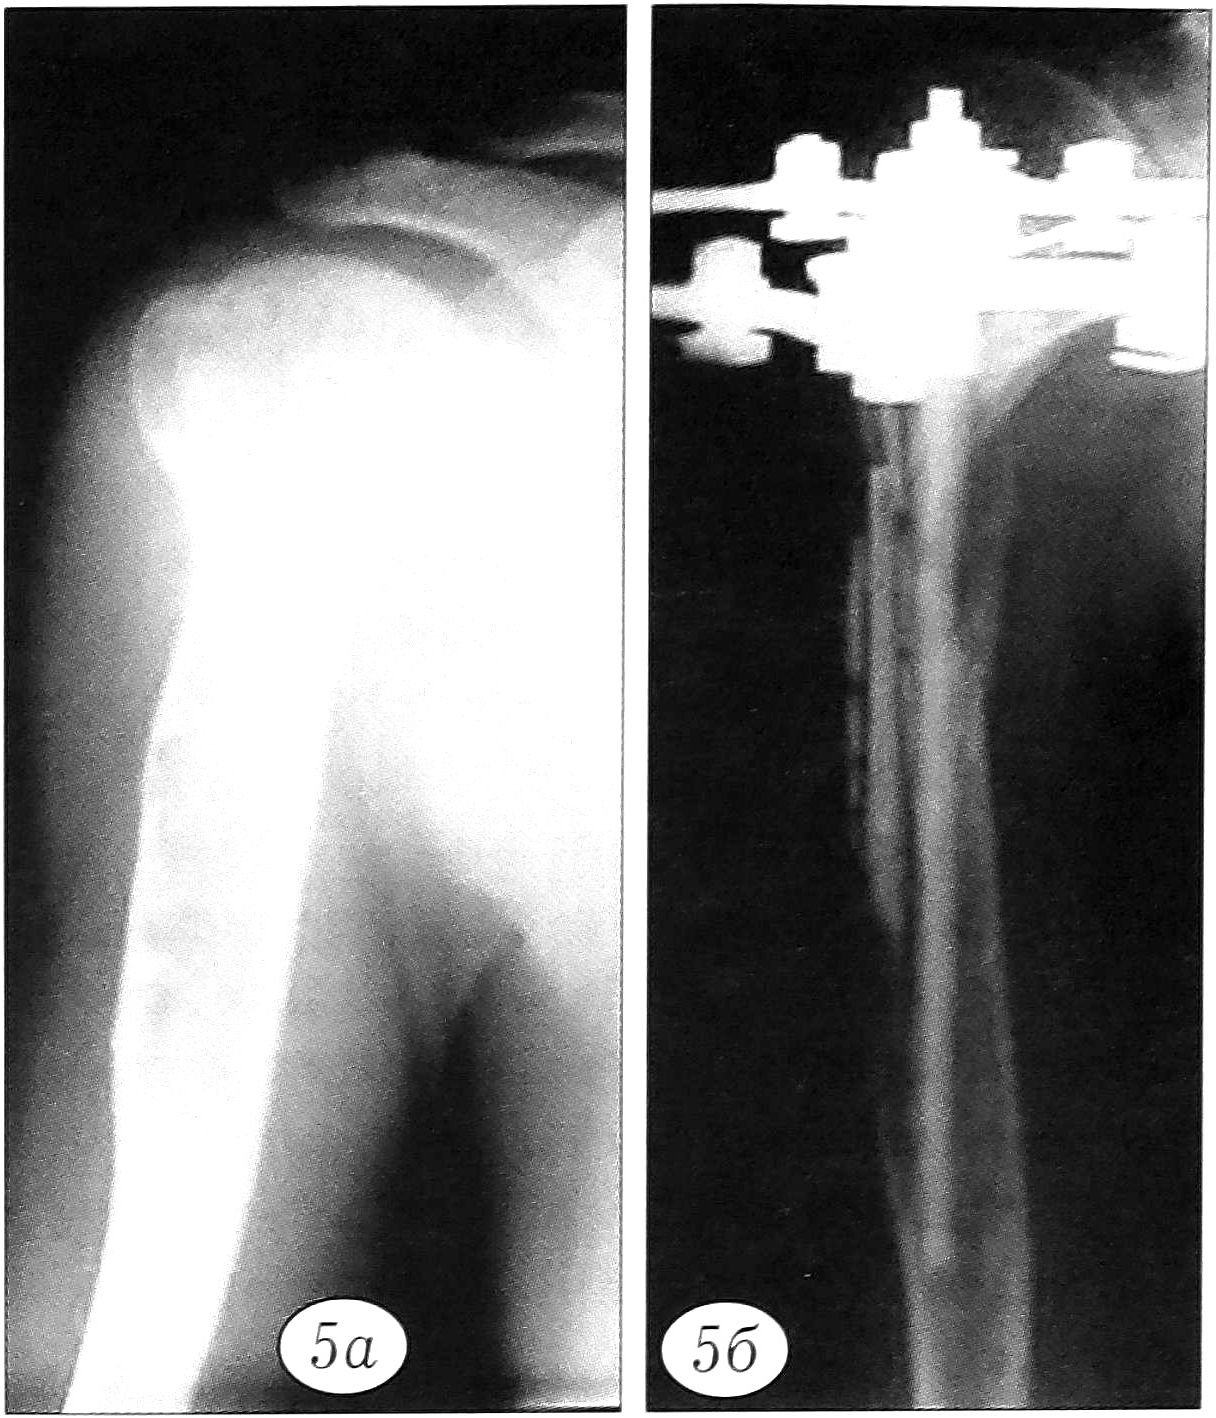

У 3 больных с несовершенным остеогенезом был произведен интрамедуллярный остеосинтез с наднадкостничной аллопластикой «Перфоостом» с целью укрепления кости и увеличения костной массы оперируемого сегмента (рис. 4).

Рис. 4. Рентгенограммы больной Ч. 11 лет. Деформации нижних конечностей на почве несовершенного остеогенеза. а — до операции; б — после наднадкостничной аллопластики «Перфоостом» в сочетании с интрамедуллярным остеосинтезом; в — через 6 мес после операции.